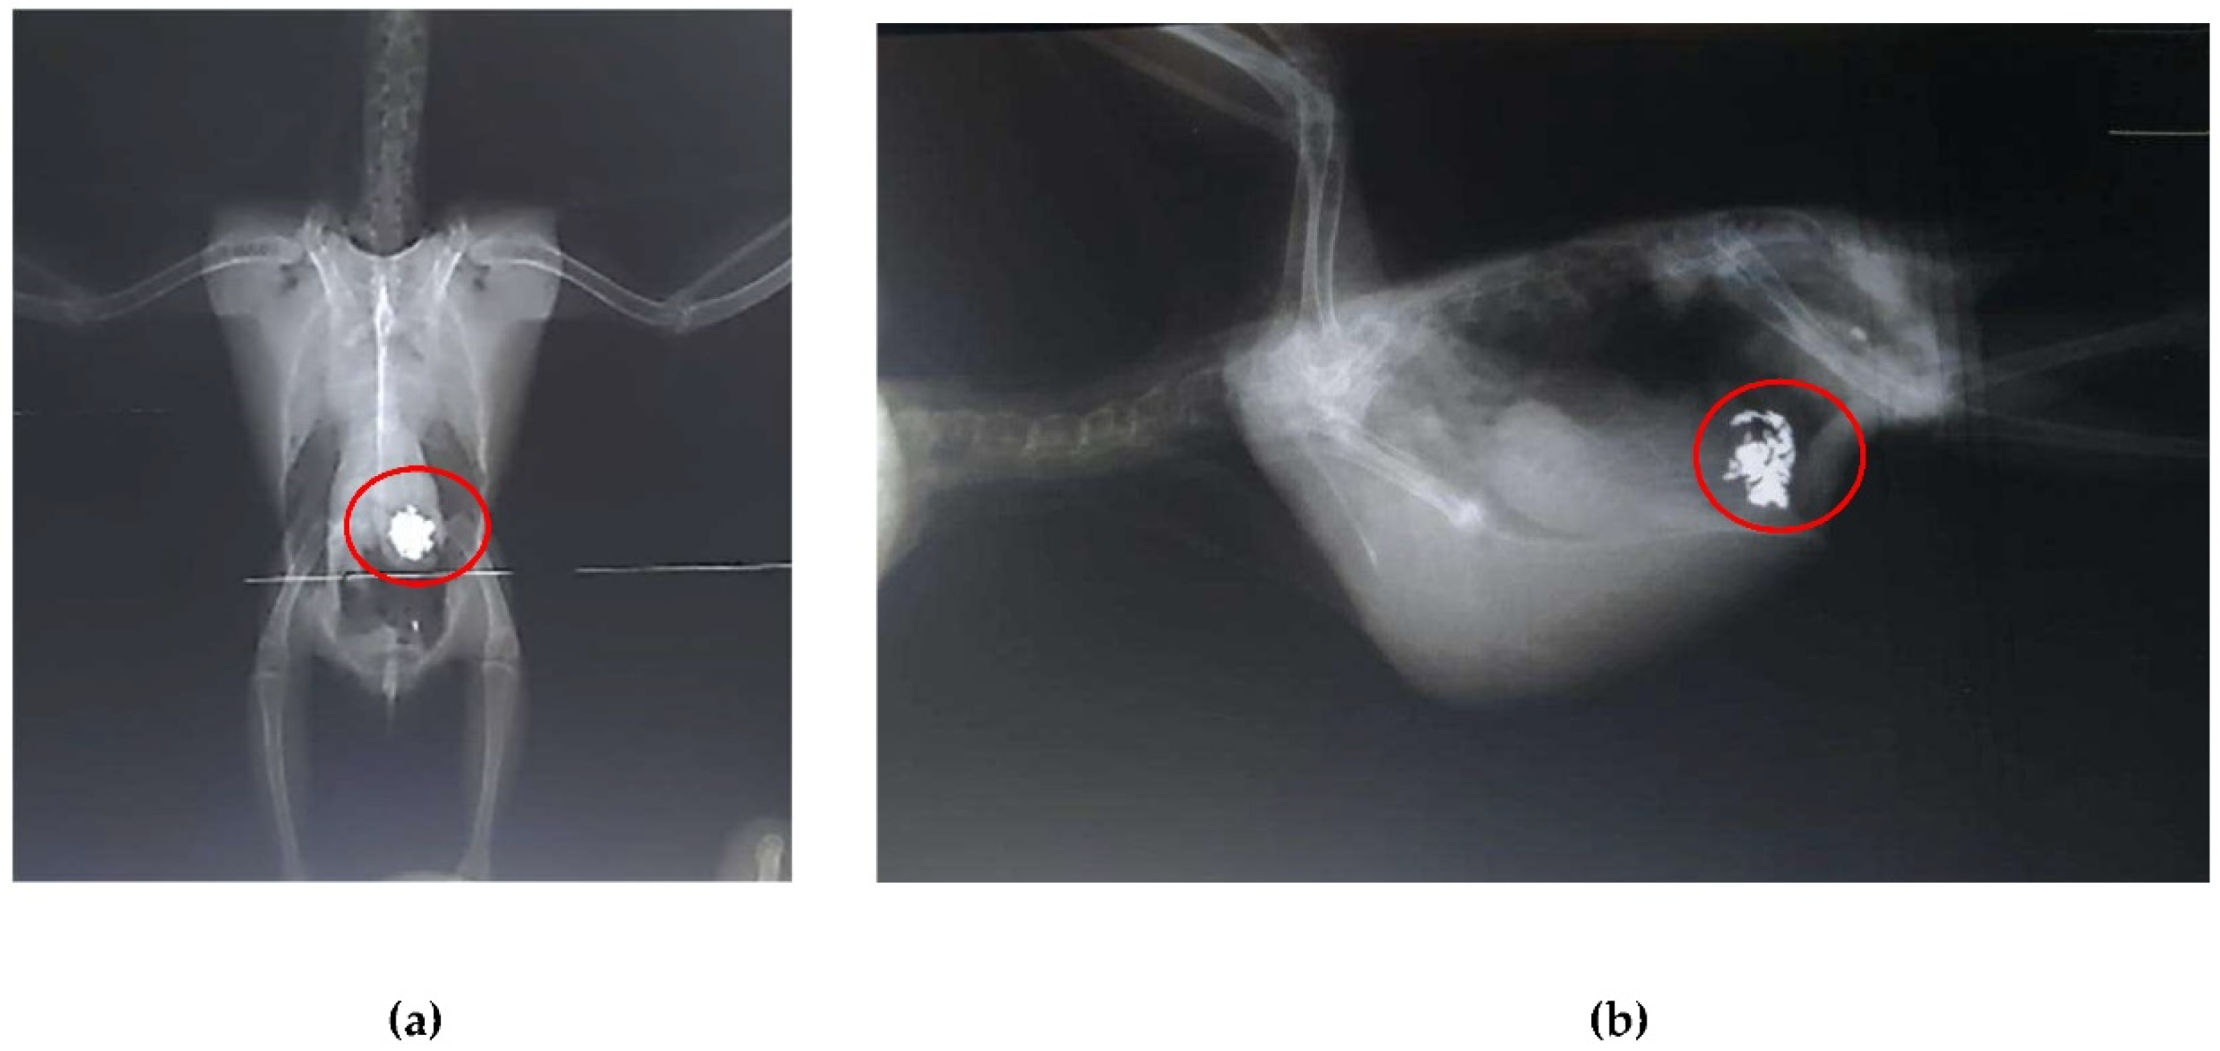

Radiographic examinations revealed a significant accumulation of radiopaque foreign bodies in the ventriculus of both birds, suggestive of metal ingestion (Figure 3A, B and Figure 4A, B). The hematological results are presented in Table 1.

Figure 4. Radiographic examination of the coelomic cavity of an Aratinga jandaya (bird 2). (a) Ventrodorsal projection – presence of a large quantity of radiopaque foreign bodies (outlined in red) in the ventricular region, suggestive of metal; increased radiopacity of the thoracic air sacs. (b) Right laterolateral projection – presence of radiopaque foreign bodies (outlined in red), also suggestive of metal.